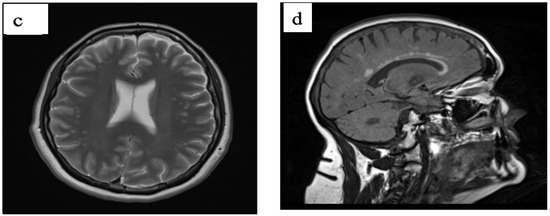

Premutation Females with preFXTAS

by Valentina Liani, Carme Torrents, Elisa Rolleri, Nor Azyati Yusoff, Narueporn Likhitweerawong, Sydney Moore, Flora Tassone, Andrea Schneider, Ellery Santos, Hazel M. B. Biag, James A. Bourgeois, Kathryn E. Unruh, Matthew W. Mosconi and Randi J. Hagerman

Fragile-X-associated tremor/ataxia syndrome (FXTAS) is a progressive neurodegenerative disorder associated with the FMR1 gene premutation, characterized by the presence of 55 to 200 CGG triplet repeat expansions. Although the initial symptoms of FXTAS typically manifest in males around the age of 60 with [...] Read more.

Fragile-X-associated tremor/ataxia syndrome (FXTAS) is a progressive neurodegenerative disorder associated with the FMR1 gene premutation, characterized by the presence of 55 to 200 CGG triplet repeat expansions. Although the initial symptoms of FXTAS typically manifest in males around the age of 60 with motor symptoms and cognitive deficits, the presentation and progression in females differ. Women, in fact, exhibit a higher prevalence of neuropsychiatric symptoms, with an earlier onset compared to the motor symptoms observed in men. The following article reports on ten cases of women with a diagnosis of FMR1 gene premutation, originating from two medical centers. All the women in the study exhibited neuropsychiatric symptoms and subtle neurological signs as common features. Symptoms typically observed in the male population, such as tremors and cerebellar ataxia, were either absent or significantly reduced in the female cohort. Conversely, there was a higher prevalence of neuropsychiatric symptoms among the women. Neurocognitive impairment was only minimally evident, with mild executive dysfunction and memory complaints noted in a subset of cases. For this reason, we propose the terminology preFXTAS or prodromic FXTAS to define a clinical presentation in women characterized by early manifestations of FXTAS that do not entirely fulfill the established diagnostic criteria but exhibit MRI evidence of white matter alterations suggesting the initiation of the disease process. The study underscores the importance of establishing new diagnostic criteria for FXTAS and, at the same time, developing new biomarkers and interview checklists/assessment scales dedicated to females. Full article